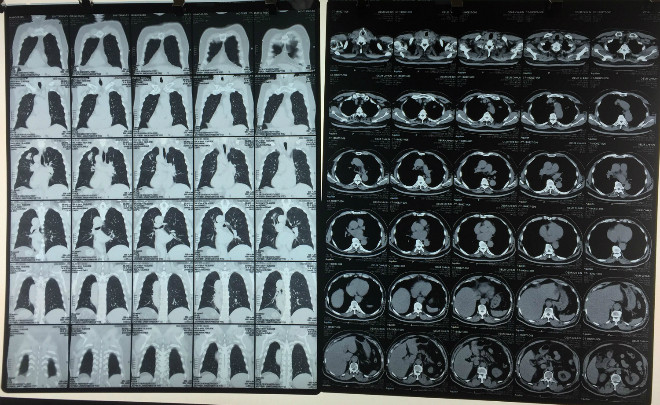

| Khối u phổi trên phim CT của bệnh nhân. |